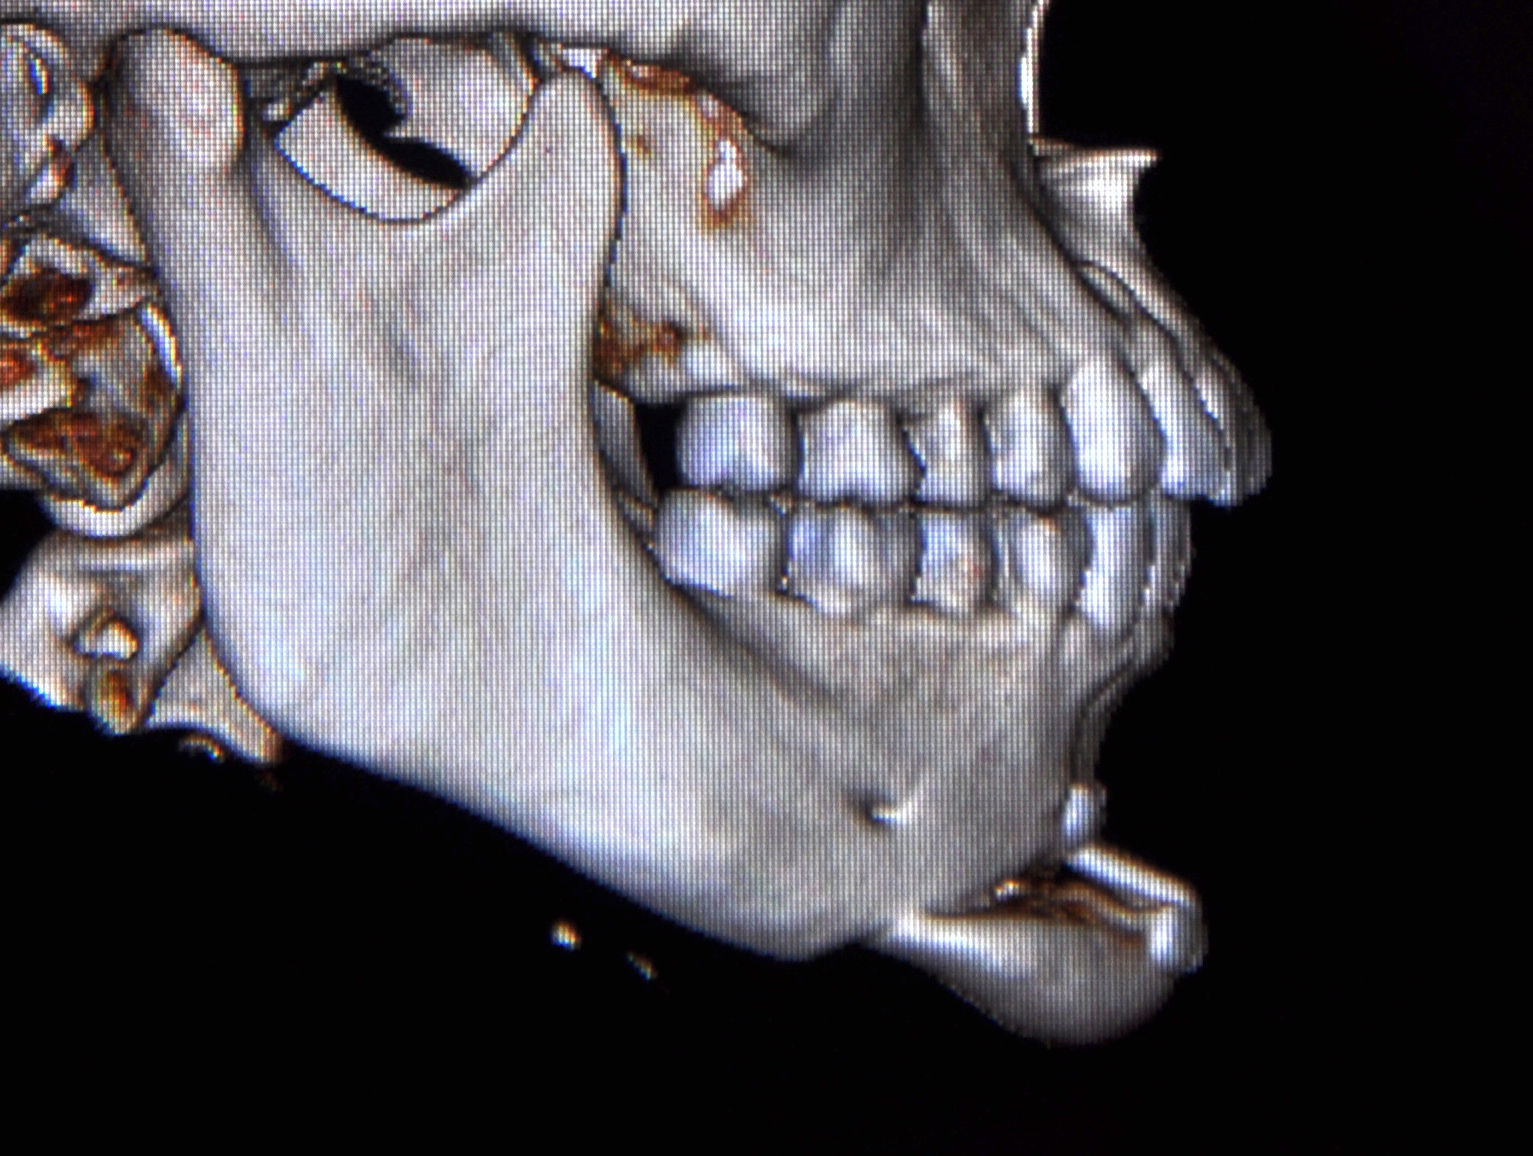

Chin reduction and rotation to address asymmetry.

Look at the transition between the chin and the mandible; clearly a step-off. Is this because of chin shaving/reduction having the opposite of a tightening effect, or just simply poor technique on Ramieri's part?

Now I DM'd a user who claims he has spoken to 5 people who got genio with Ramieri, and all of them had a combo or at least an issue with asymmetry and step-off, even with conservative movements.

Genio is supposed to be a relatively simple surgery, and hard to mess up. Is it really just poorly planned cuts or something else about the technique? Or is the step-off exaggerated in these after photos because of soft tissue swelling? Is the problem case-specific, or is Ramieri generally bad at genioplasties? I don't think it's fair to judge based on 2 cases and a few supposed forum anecdotes, but it doesn't set a good precedent for sure.